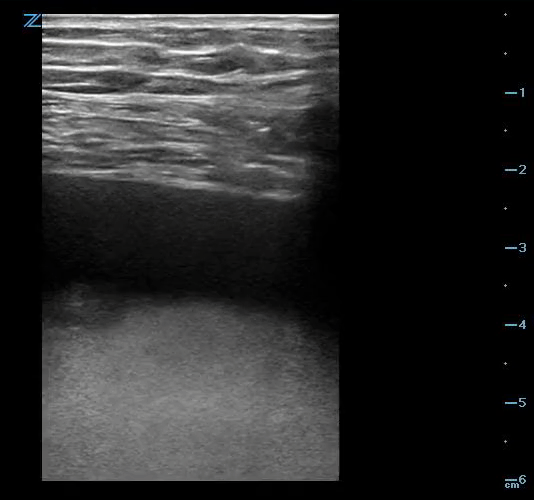

• Use high-frequency (linear) probe!!

• Shortest skin to pericardium distance

• Complication: pneumothorax, ventricular puncture

Apical approach: Introduce needle over the superior border of the adjacent rib to avoid intercostal nerves/vessels. Needle is introduced lateral to ribs 5-7. Aim towards the patient's right shoulder.

Pericardiocentesis: apical approach. Needle visualized top right of screen.

Apical approach using high-frequency probe. Needle visualized top right of screen.